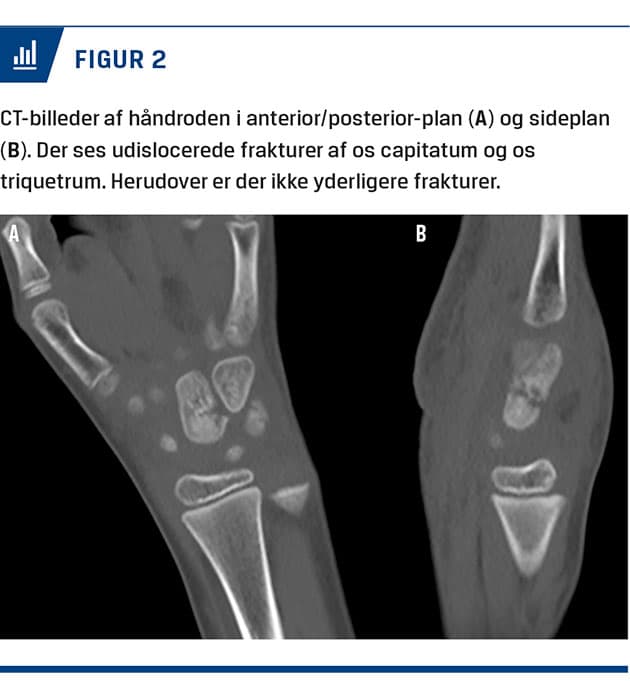

En syvårig dreng blev behandlet på skadestuen efter at have fået klemt venstre hånd mellem kanten af et skolebord og gulvet. Ved en objektiv undersøgelse fandt man misfarvning både dorsalt og volart over håndroden. Han var tydeligt smertepåvirket ved både direkte og indirekte undersøgelse af håndroden. Bevægeligheden i hånden var ophørt pga. smerter. En røntgenoptagelse viste fraktur af os capitatum og os triquetrum (Figur 1). Samme dag blev der foretaget CT af venstre hånd for verificering af diagnosen samt udelukkelse af øvrige frakturer og dislocering med betydning for behandlingen (Figur 2). Frakturerne i os capitatum og os triquetrum var udislocerede og egnede til konservativ behandling. Der blev anlagt en dorsal gipsskinne. Ved ambulant kontrol syv dage posttraumatisk var der bedring smertemæssigt. En røntgenoptagelse viste uændret stilling af frakturerne. Ved ambulant kontrol fire uger efter traumet viste en røntgenoptagelse begyndende kalcifikation af frakturen, klinisk var der smertefrihed. Patienten blev henvist til ergoterapi. Efter seks måneder havde han normal bevægelighed og god kraft i

håndroden ved belastning.